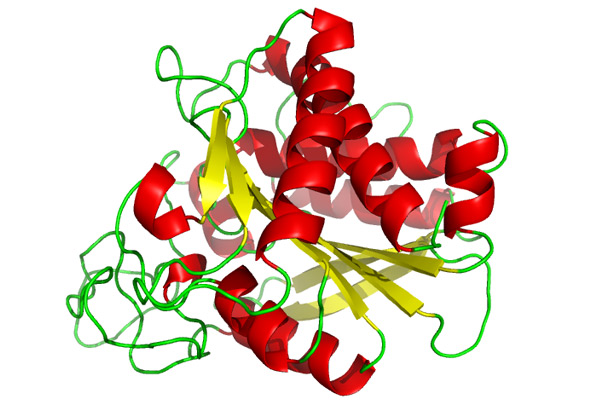

Μετά την αποφοίτησή μου ετάχθην σε ερευνητικό πρόγραμμα του ανωτέρω Πανεπιστημίου υπό την επίβλεψη του καθηγητή Πανεπιστημίου Παθολογικής Ανατομικής Dezso Balazs, ο οποίος επέβλεψε και κατηύθυνε την έρευνά μου. Το σχέδιο έρευνας που κατέθεσα αξιολογήθηκε από τη Feichtinger Foundation με συνακόλουθη απόφαση για χρηματοδότηση του μέχρι ολοκλήρωσης του, απόφαση ιδιαιτέρως τιμητική για μένα.